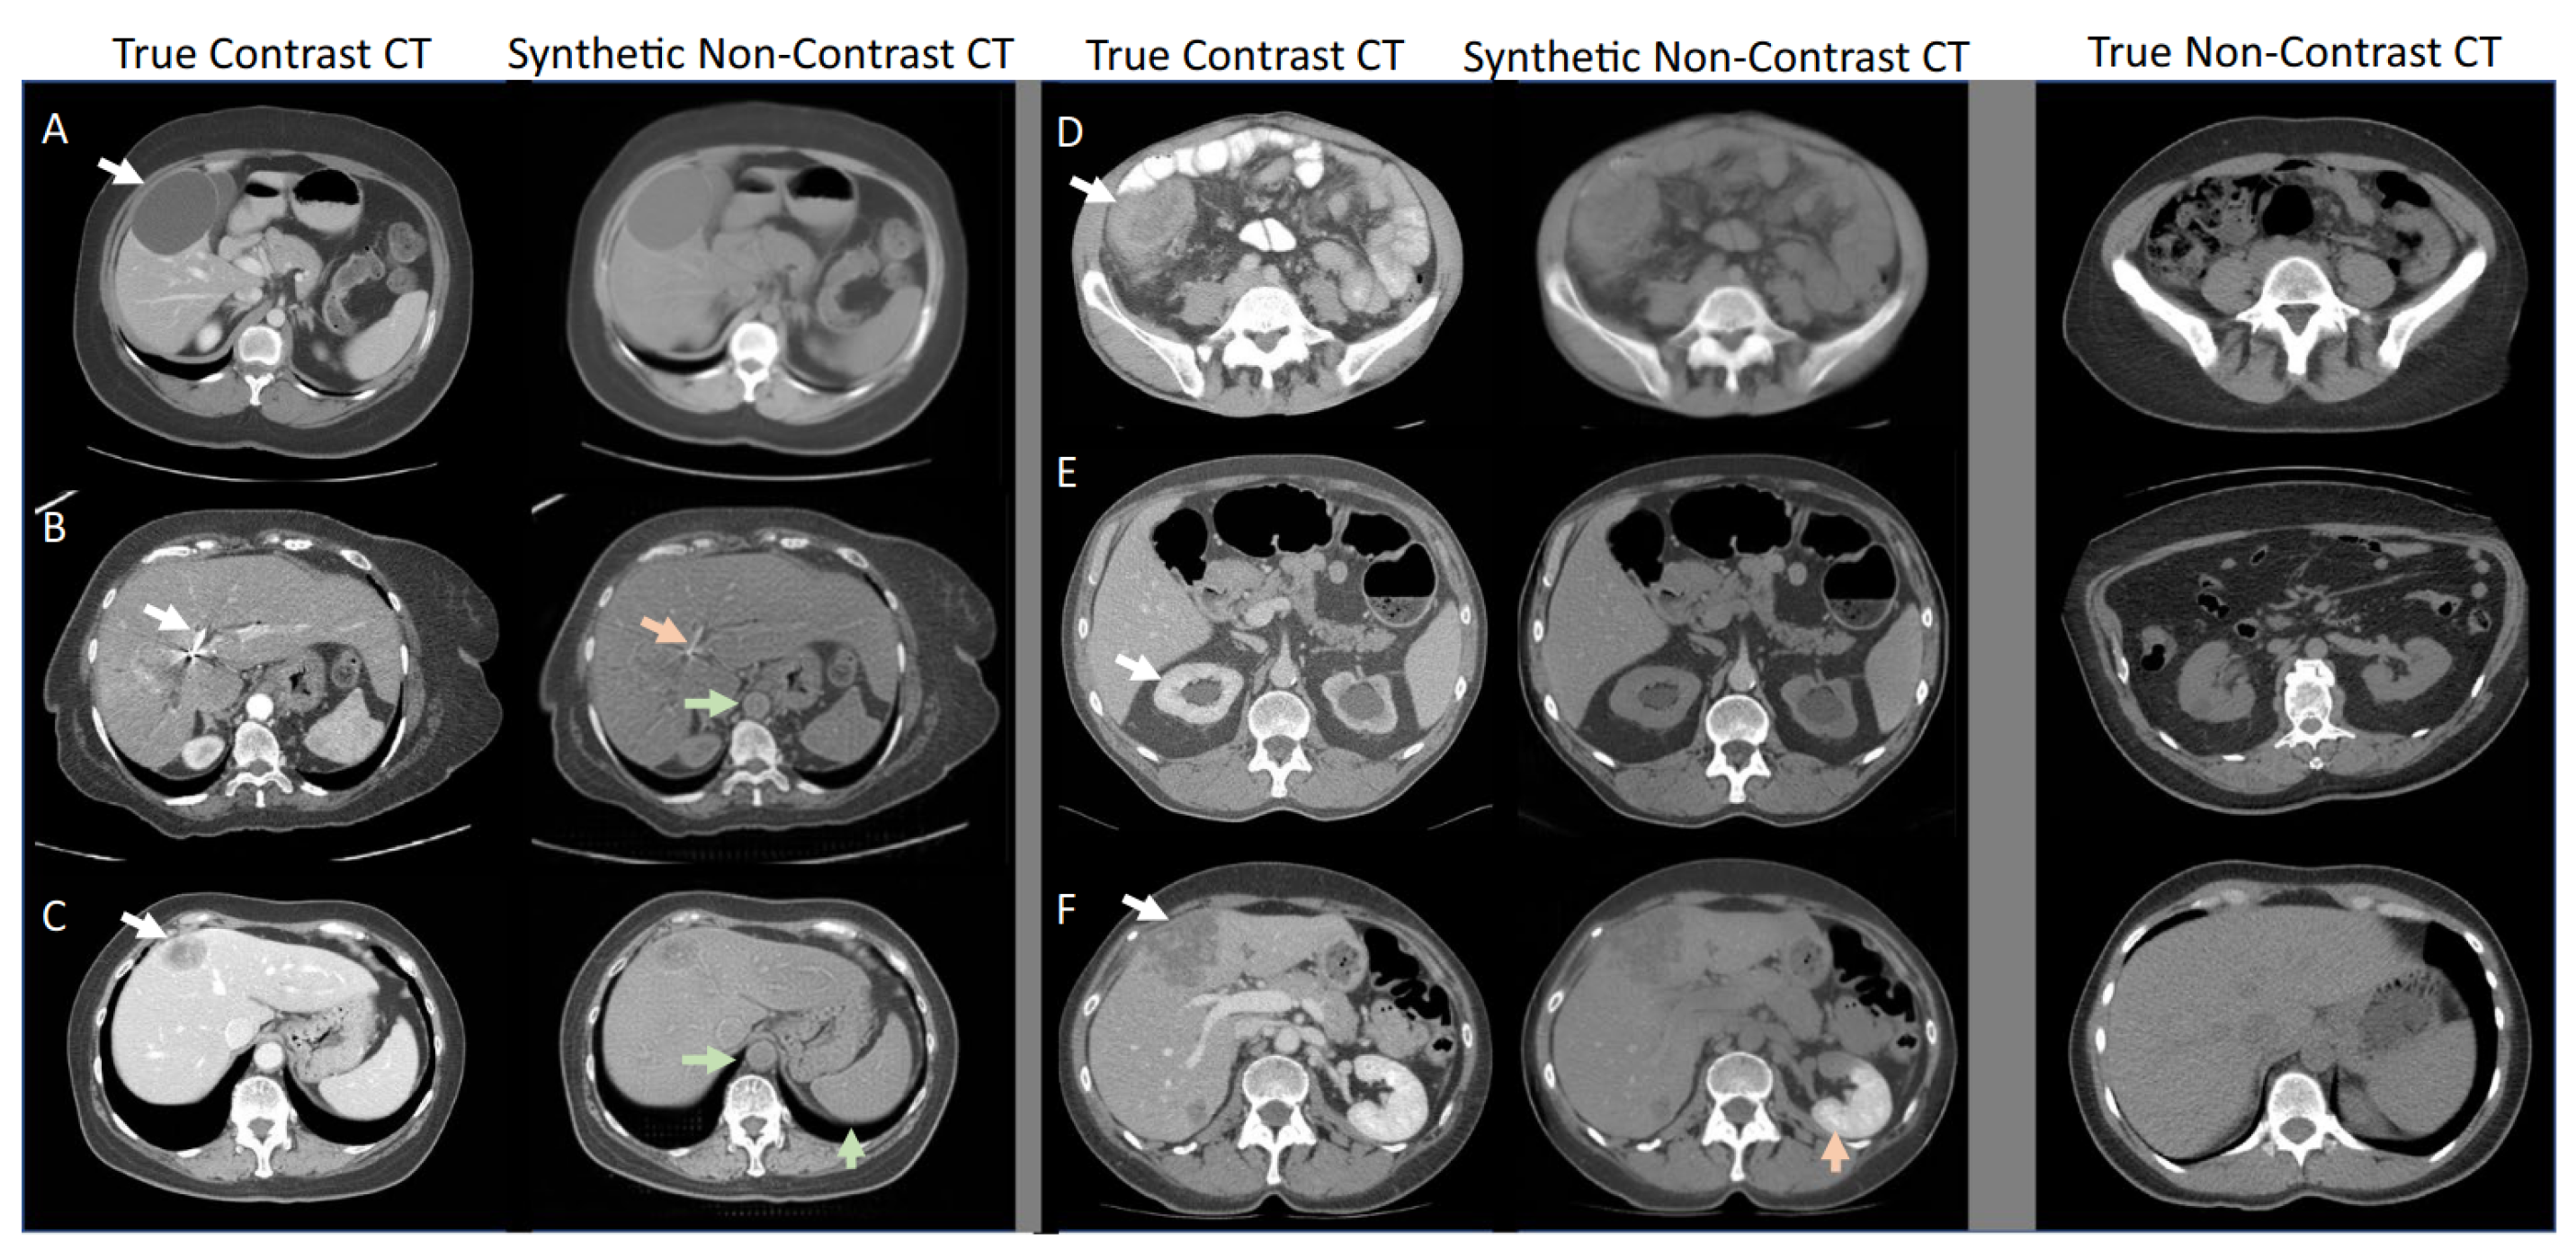

Figure 3.

Adapted from Sandfort et al. [12], the study presented examples of true contrast CT scans and synthetic non-contrast CT scans generated using a CycleGAN. The left columns show the true contrast CT scans, while the right columns present the synthetic non-contrast CT scans. It is observed that the synthetic non-contrast images generated with CycleGAN appeared convincing, even in the presence of significant abnormalities in the contrast CT scans. The last column on the right displays unrelated examples of non-contrast images. The letters A to F in this figure represent various abnormalities/pathologies, and the arrows indicate their corresponding synthetic non-contrast CT images. However, they are not essential for understanding the main purpose of the figure, which is to demonstrate the generator's ability to produce realistic images.